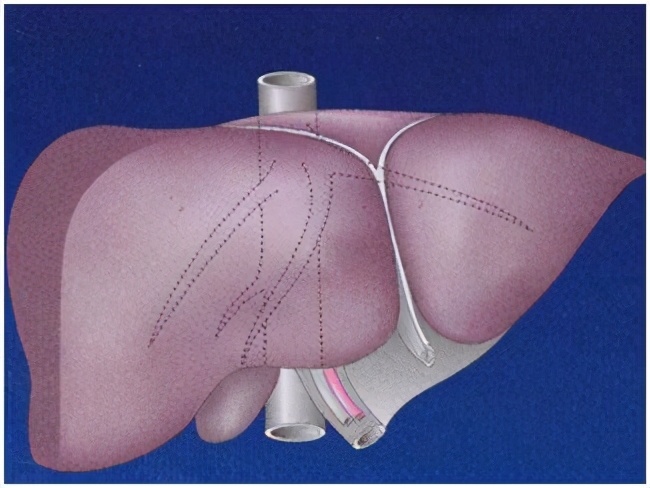

手术的办法包括:肝部分切除、血管瘤剜除术、肝动脉结扎和肝脏移植等。